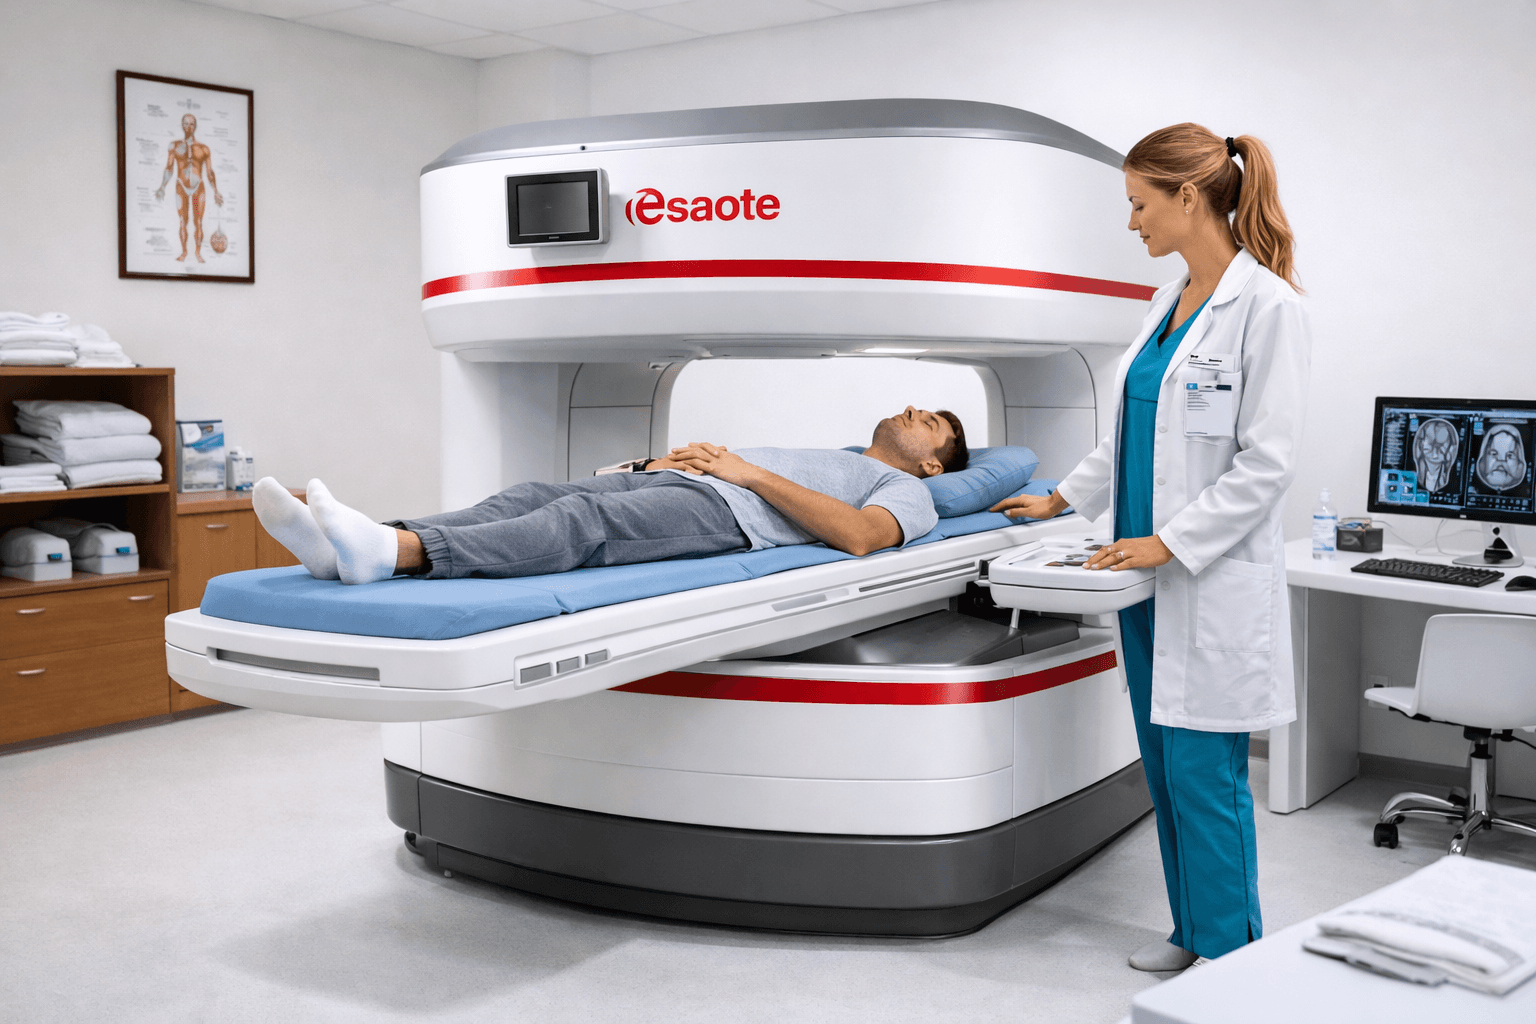

Resonancia Magnética Abierta

Equipo Esaote Magnífico Open. Diagnóstico especializado para lesiones osteoarticulares, ideal para pacientes claustrofóbicos y niños.

Esaote Magnífico Open

Resonancia abierta

Imágenes más detalladas y precisas con lo último en equipos médicos.